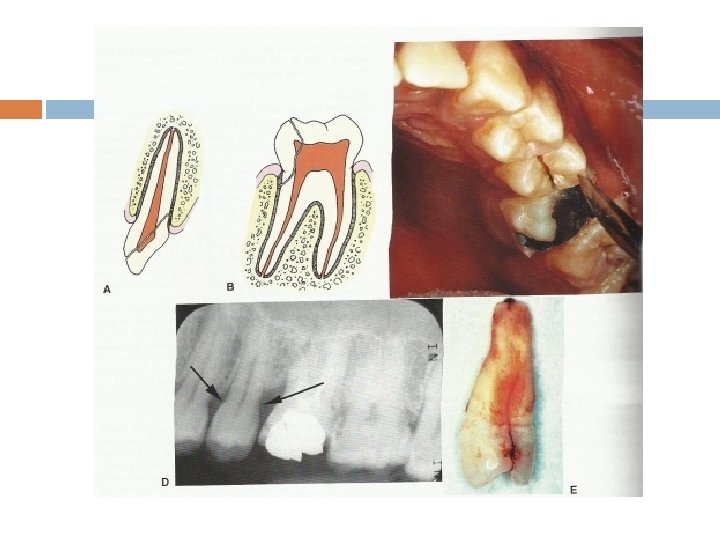

Periapical X ray

Abscess adjacent to primary tooth

Anatomic location

Caries and periapical lesion

pericoronitis